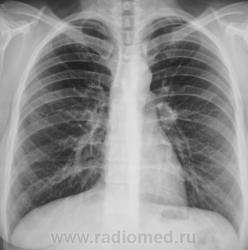

Какие мнения, уважаемые коллеги, будут по рентгенограмме?

я думаю здесь норма

1. На уровне переднего отрезка 1-го ребра справа (под ключицей) - подозрение на очавую тень

2. На уровне переднего отрезка 4-го ребра справа - похоже на консолидированый перелом.